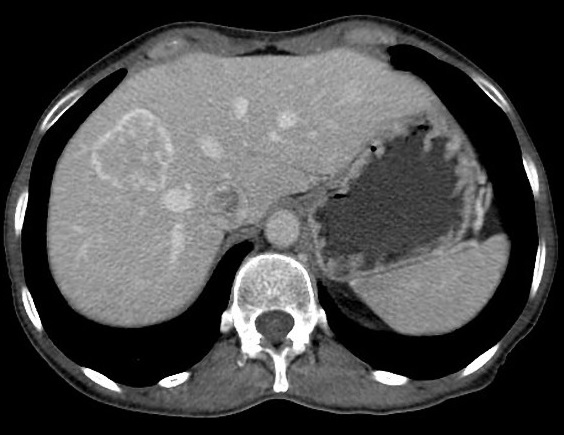

Image radiologique TDM d'une kyste simple

du foie droit en coupe axiale : Aspect

lesionnel a densite variee de 7-15 UH ( hypodense )

avec bord lisse , bien definie et regulier |

Même cas en coupe coronal (

fleche rouge ) . La kyste est situe du foie droit

juste a inferieuse du coupole diapragmatique droit |